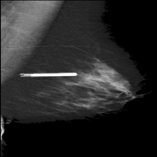

The 136 true outliers are classified into seven categories by the professional radiologist: implant, pacemaker, cardiac loop recorder, improper radiography, atypical lesion/calcification, incorrect exposure parameter and improper placement. It is worth noting that, despite the fact that mammograms with implants were eliminated during the preprocessing step (see Section 2.6), there were still mammograms with implants remaining since they were incorrectly categorised as having no implants. Figure 1 depicts representative outliers for each category, and Table. 4 displays the number and percentage of outliers in each category given that that the total number of true outliers is 136.

Figure 1: Examples of true outlier subgroups in the ADMANI dataset. From left to right and top to bottom, the outlier types are: implant, pacemaker, cardiac loop recorder, improper radiography, improper radiography, atypical lesions/calcification, incorrect exposure parameter, improper placement. Improper radiography is classified into two subtypes: those with heterogeneous pectoral muscle and the rest, respectively.